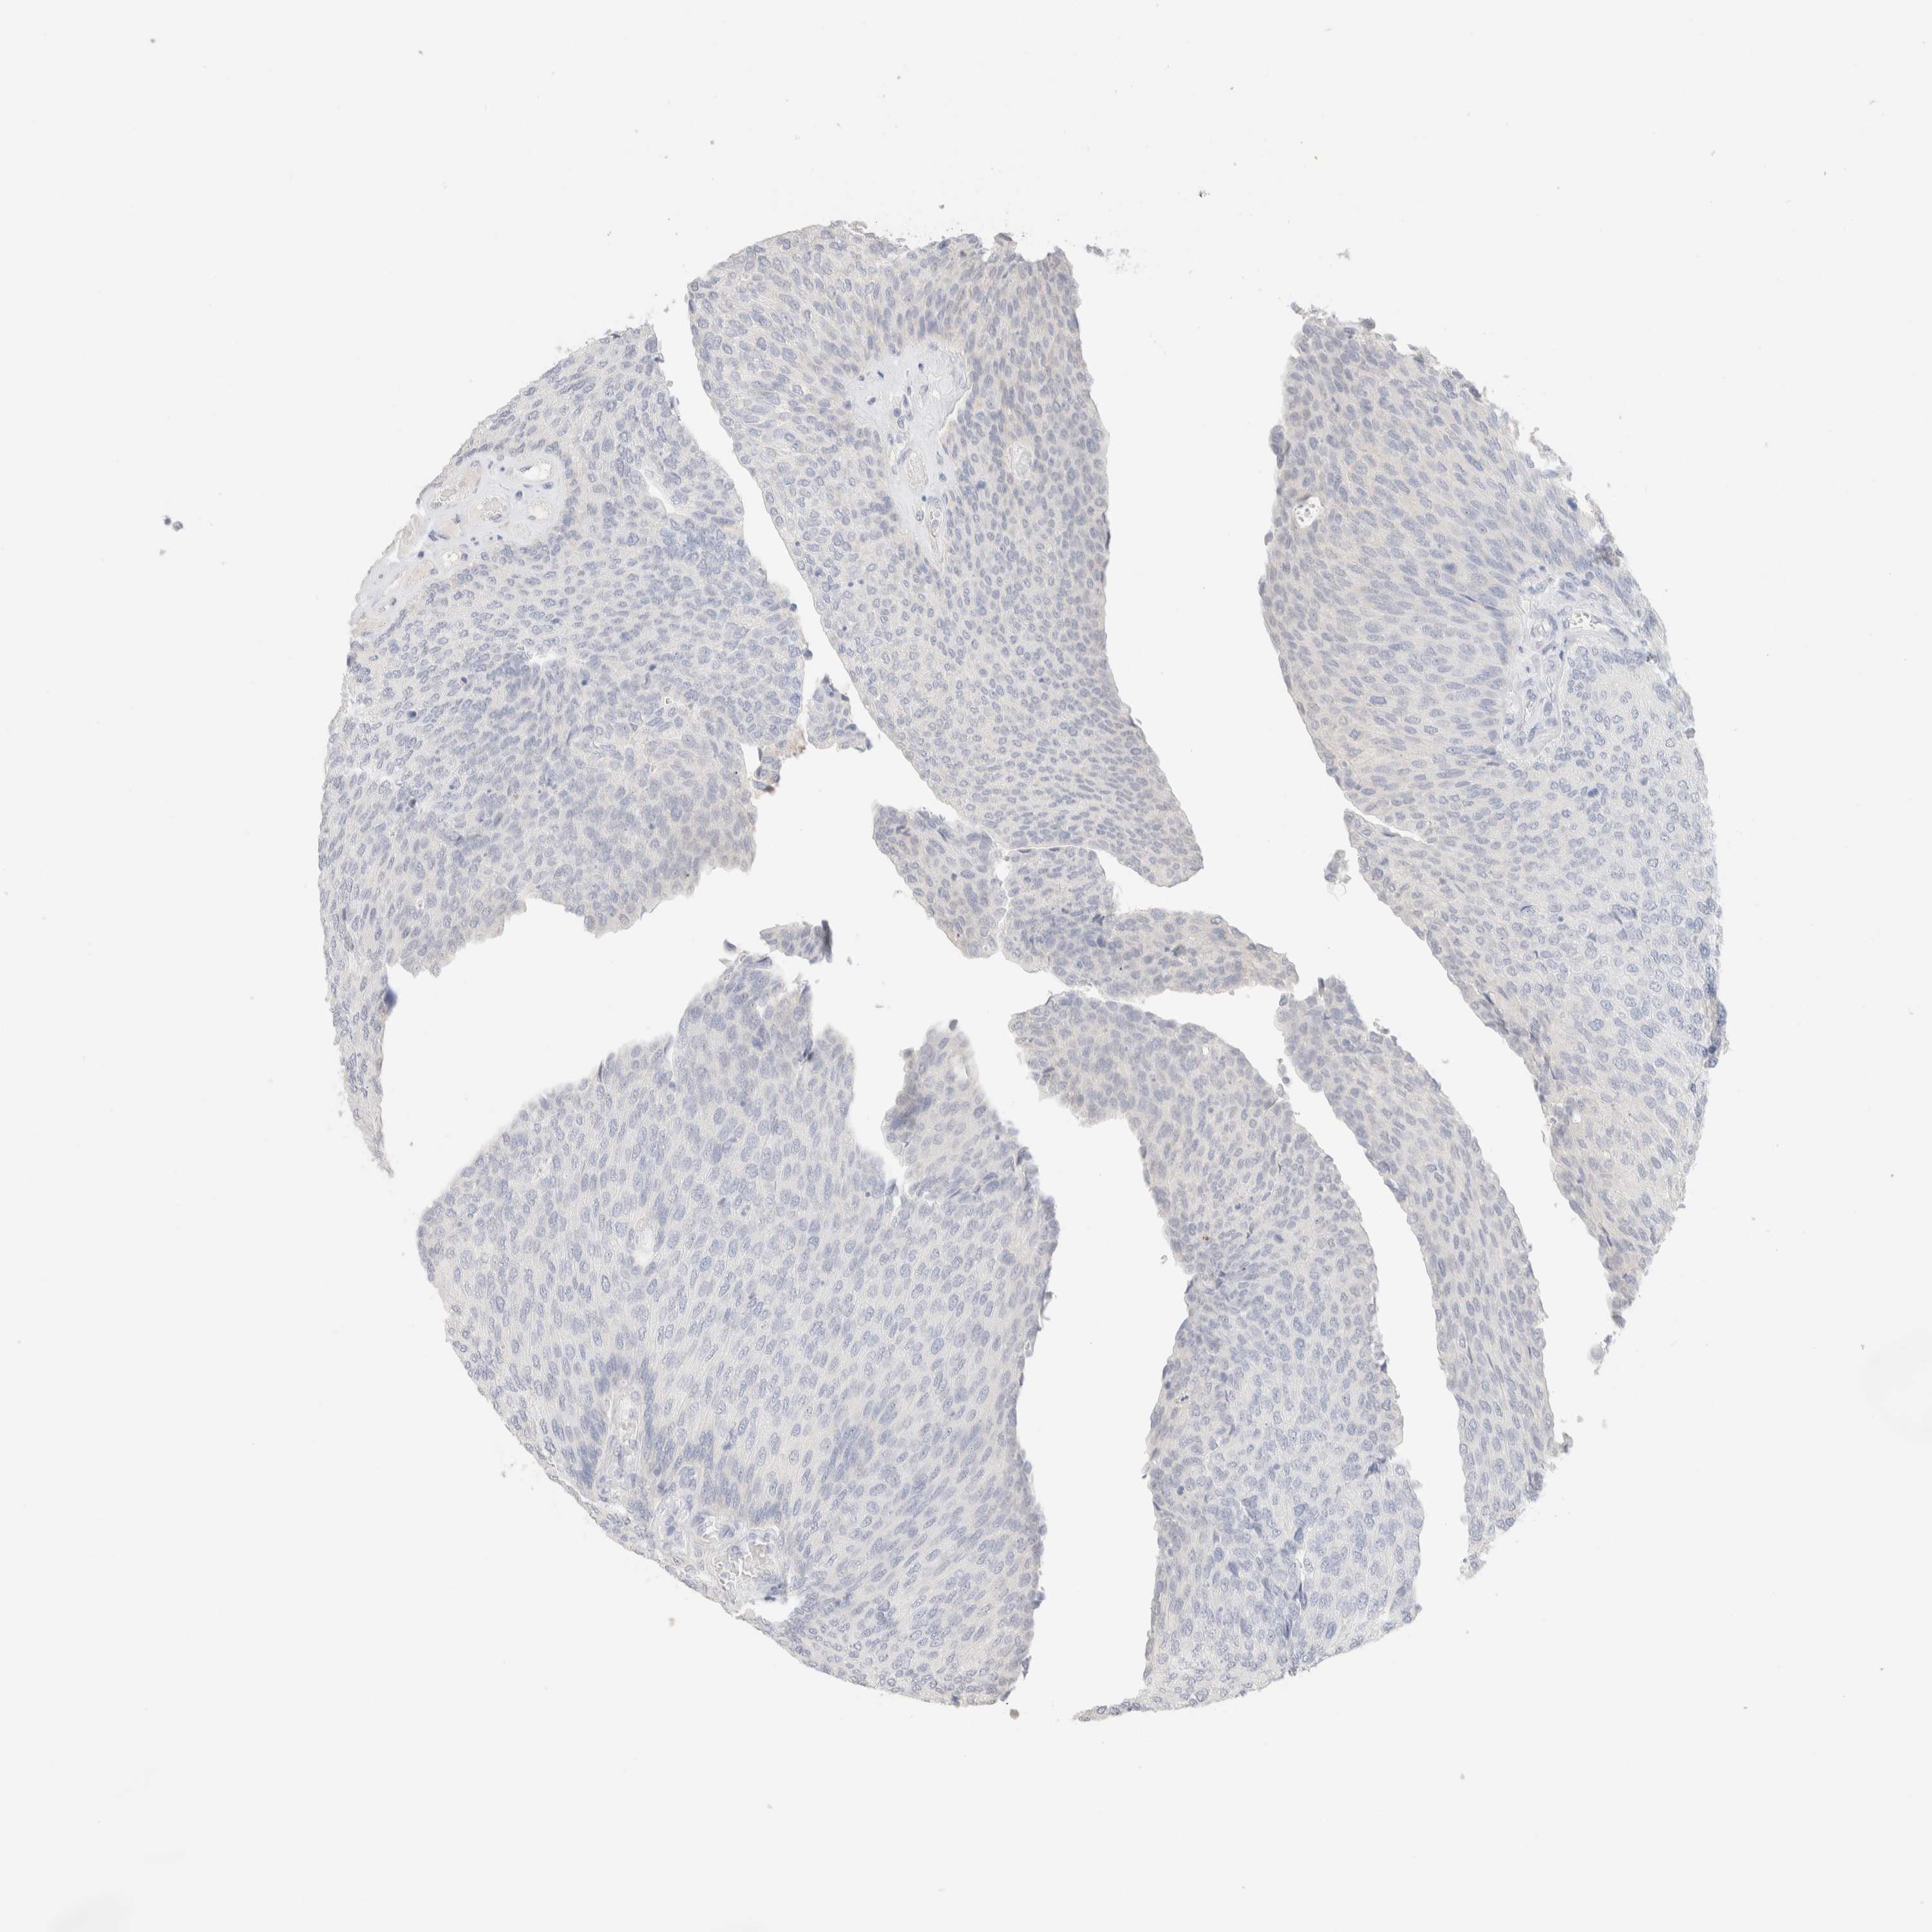

UROTHELIAL CANCER - Protein expressioni

A mouse-over function shows sample information and annotation data. Click on an image to view it in a full screen mode. Samples can be filtered based on level of antibody staining by selecting one or several of the following categories: high, medium, low and not detected. The assay and annotation is described here.

Note that samples used for immunohistochemistry by the Human Protein Atlas do not correspond to samples in the TCGA dataset.

Antibody stainingi

Antibody staining in the annotated cell types in the current human tissue is reported as not detected, low, medium, or high, based on conventional immunohistochemistry profiling in selected tissues. This score is based on the combination of the staining intensity and fraction of stained cells.

Each image is clickable and will lead to virtual microscopy that enables deeper exploration of all samples and also displays staining intensity scores, fraction scores and subcellular localization as well as patient and tissue information for each sample.

Antibody HPA022856

Antibody HPA023489

Urothelial carcinoma, Low grade

Urothelial carcinoma, High grade